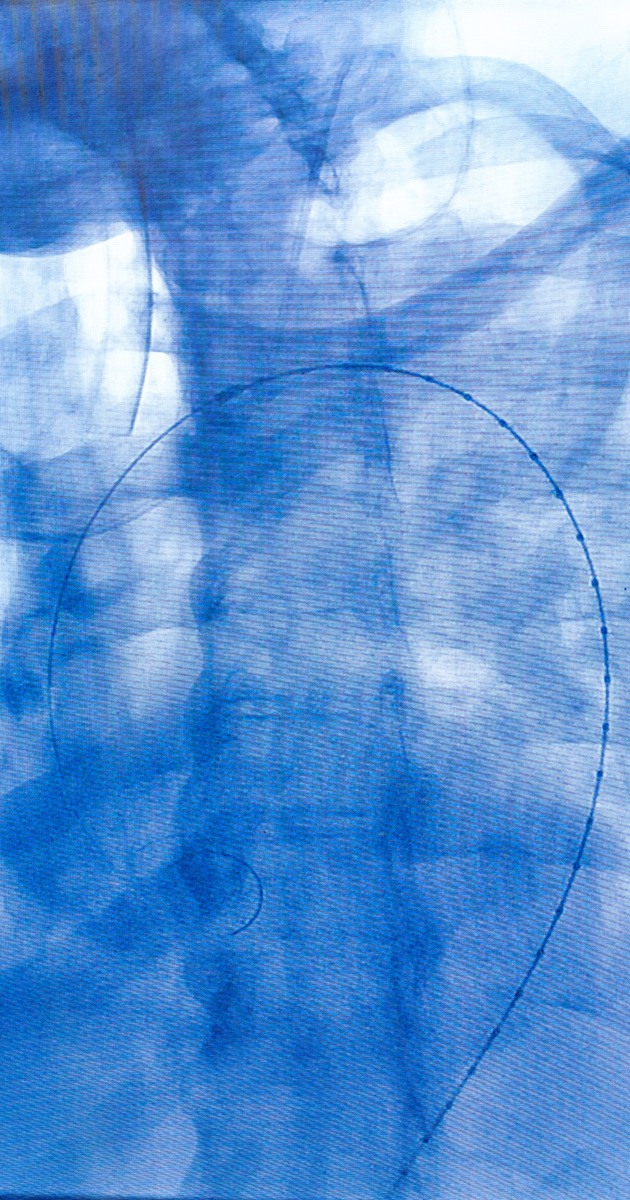

The team successfully performed an endovascular stent graft procedure designed to reinforce weakened blood vessel walls by inserting a stent graft through a catheter via a minimally invasive approach. They utilized the Zenith Alpha 2.0 Thoracic Endovascular Graft, developed by Cook Medical, known for its advanced capabilities in complex aortic repairs.

What made this surgery especially pioneering was the use of CO₂ flushing, a departure from the traditional heparinized saline. This technique minimizes the introduction of excess oxygen, significantly reducing the risk of microembolic events—tiny air bubbles that can travel to the brain and cause strokes. By combining this new approach with the advanced graft design, the team has addressed one of the most critical risks in aortic surgery.

This procedure successfully treated a complex Type B aortic dissection—an often undiagnosed, life-threatening condition. Thanks to the minimally invasive approach and the expert care provided by the Institute for Cardiovascular Health care team, the patient was discharged just three days after surgery, showcasing the safety and efficacy of the method.

The use of CO₂ flushing alongside the Zenith Alpha 2.0 Thoracic Endovascular Graft is setting a new benchmark for patient safety. By reducing the risk of stroke from microembolic events, the Institute for Cardiovascular Health is pioneering a new era in cardiovascular care. This forward-thinking approach reflects the team’s unwavering commitment to patient-centered care and continuous innovation.